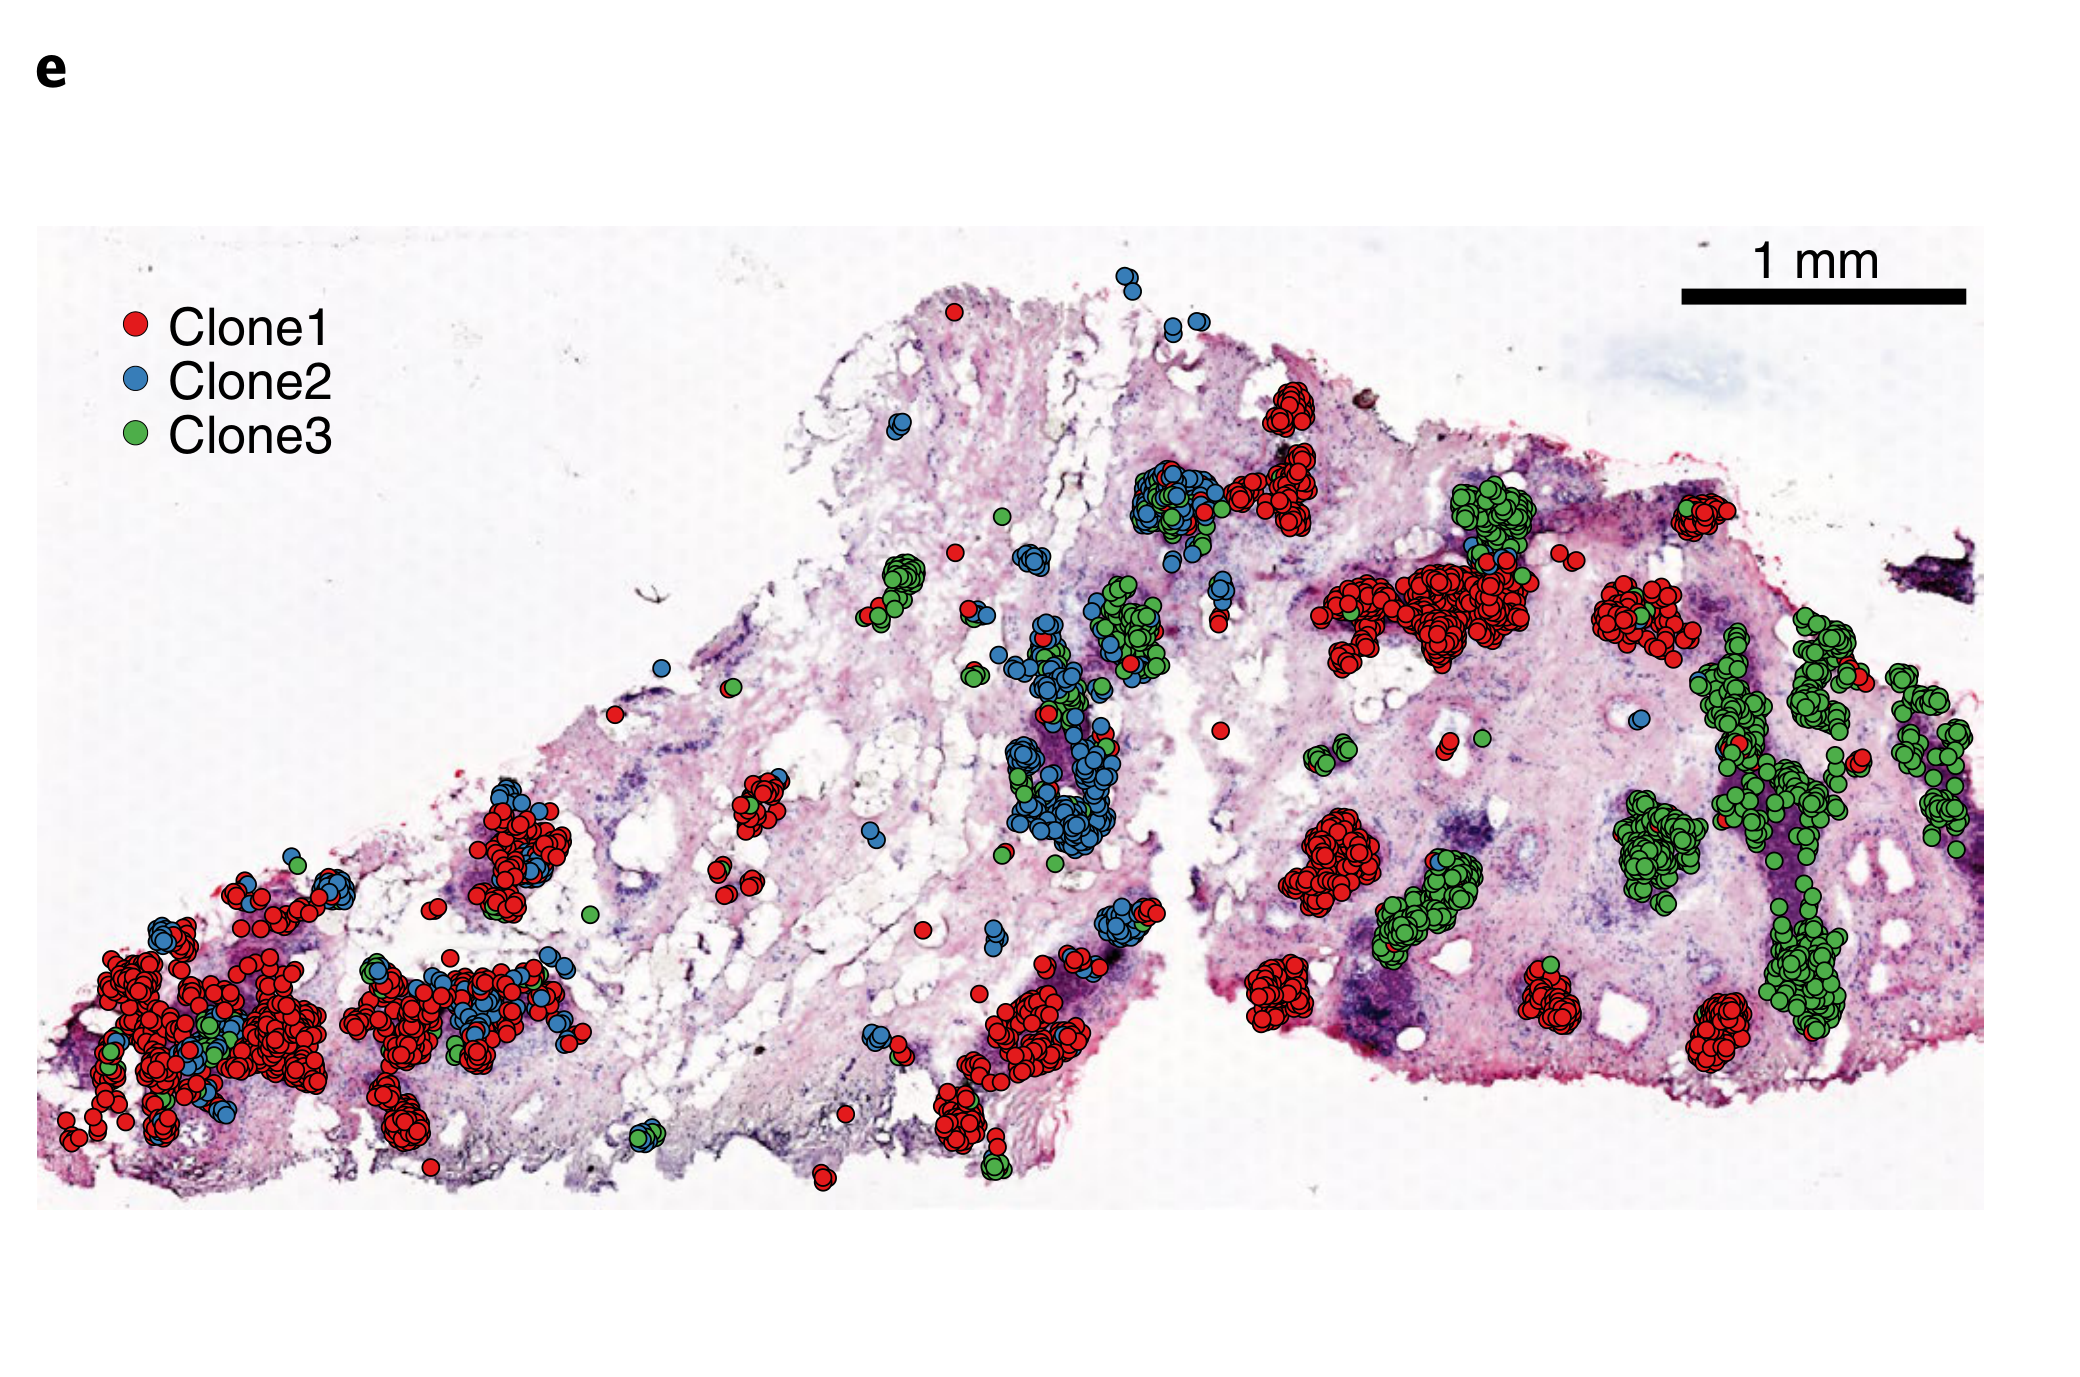

Wei R. et al. - 2022

Spatial charting of single-cell transcriptomes in tissues

How are tumor subclones spatially distributed within a tissue section?

Biological

Chart Type

Communicative/Contextualization

Comparative Design

Layout

Scalability Strategy

None (Item-level)